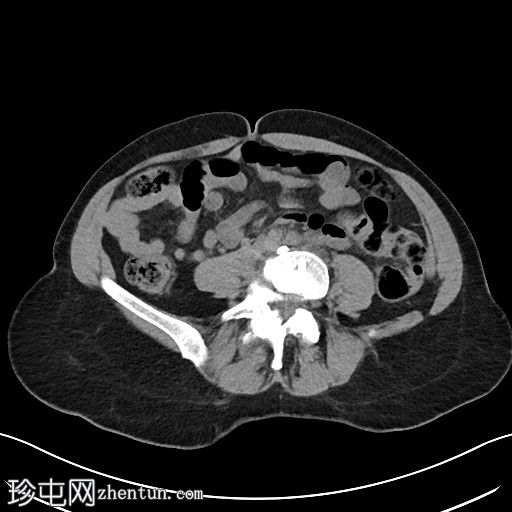

轴位

平扫

左侧腹膜后可见一巨大囊性肿块,位于左侧腰大肌内侧,紧邻多个手术夹(ALIF手术所用),这些手术夹紧贴囊性肿块后壁。

膀胱已行引流管减压,并被囊性肿块向右侧推移。

子宫和左侧附件在囊性肿块前方保持正常的脂肪间隙,因此附件囊性病变的可能性较小。

左侧输尿管难以辨认,因为它位于囊性肿块下缘后方。